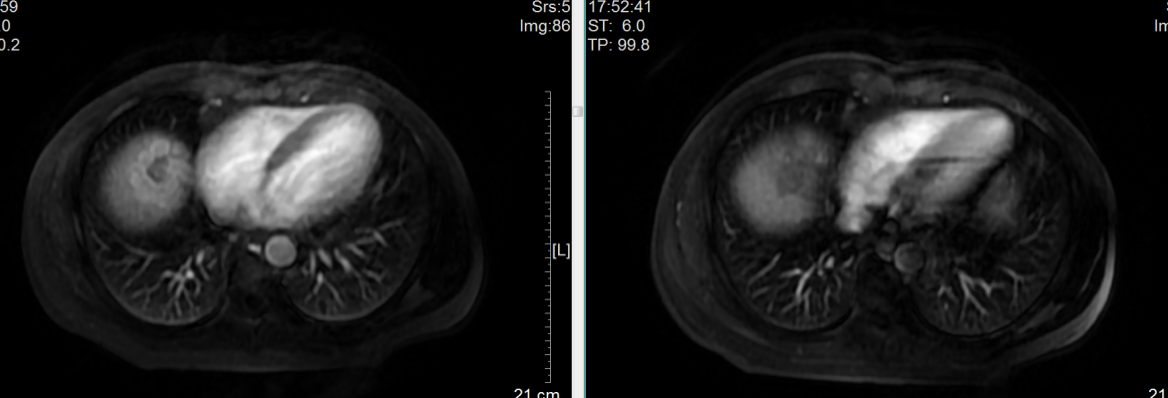

磁共振检查显示肿瘤位处肝脏膈顶部

MRI显示疗效达到完全缓解(CR)